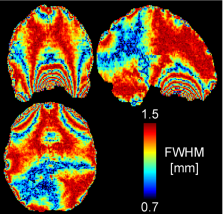

As a rule of thumb, every resampling step can lower the resolution by about the voxel size. This resampling dependent blurring has been reported in the literature from time to time and is gaining a lot of extra attention in the context of layer-dependent fMRI. Ville Renvall showed this effective resolution loss due to spatial resampling in the context of distortion correction in the supplementary material of his paper. Later, Jonathan Polimeni also showed it for motion correction.

Strategy 3: Applying spatial resampling on a finer grid than the voxel size

Since the resolution loss is a direct result from the signal redistribution of finite voxel sizes, it could be theoretically minimized by using a finer voxel grid. Finer than the effective resolution.